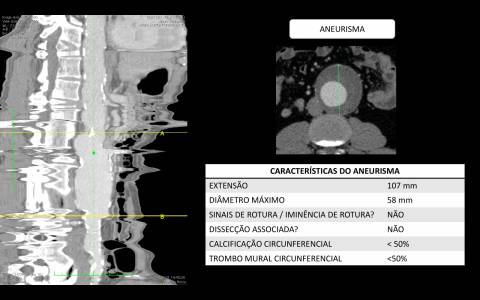

Paciente masculino 74 anos foi diagnosticado incidentalmente com aneurisma de aorta abdominal infra-renal durante ultrassonografia de abdome solicitada para avaliação clínica geral.

A avaliação por tomografia computadorizada evidenciou um aneurisma infra-renal de colo hostil e acessos vasculares com muita ateromatose. Diante do contexto clínico e de imagem foi optado pelo tratamento endovascular com endoprótese de baixo perfil Incraft CORDIS e técnica de Snorkel Grafts com stents Palmaz CORDIS para as artérias renais.